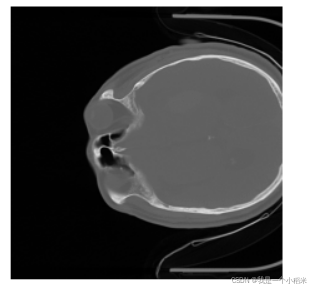

显示某一层的图像

这里的12指的就是第三维度为12 的

plt.imshow(image_data1[:, :, 12], cmap='gray')

plt.axis('off');